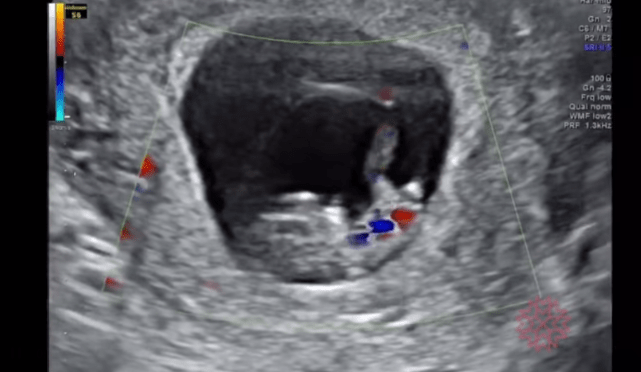

心跳

很療癒